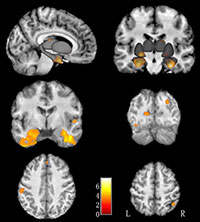

The researchers found larger gray matter volumes in multiple brain regions, especially in emotional brain circuitry, in the left-behind children compared to children living with their parents. The mean value of IQ scores in left-behind children was not significantly different from that of controls, but the gray matter volume in a brain region associated with memory encoding and retrieval was negatively correlated with IQ score.

Since larger gray matter volume may reflect insufficient pruning and maturity of the brain, the negative correlation between the gray matter volume and IQ scores suggests that growing without parental care may delay brain development.